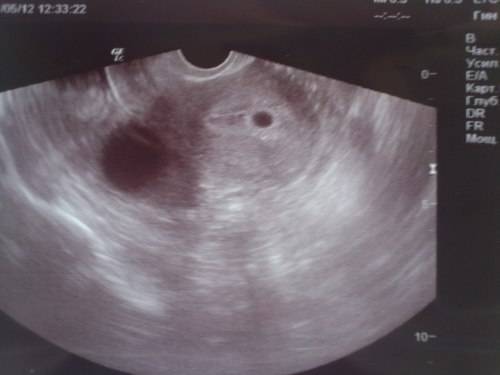

Иногда на шестой неделе беременности при трансвагинальном УЗИ можно зафиксировать биение сердца (или даже двух!). Тем не менее с какой-либо точностью о присутствии второго ребенка можно будет говорить только после УЗИ на 12-й неделе.

Для диагностики различных состояний, врачи часто используют УЗИ. Будущей маме предстоит регулярно проходить такое обследование. Именно этот метод позволит узнать, сколько малышей находится в матке. Стоит выяснить, когда можно определить двойню по УЗИ. Специалист может увидеть количество эмбрионов примерно в 5-6 недель. Но по разным причинам на маленьком сроке устанавливают, что в матке несколько плодов, не всегда. В ряде случаев врач точно диагностирует этот факт позже, например, во время скрининга в первом триместре.

С большой вероятностью двойня на УЗИ заметна после 5-ти недель, если совершается передвижение зародыша по направлению к матке и визуализируется два черных пятнышка. Обследование по УЗИ назначает личный гинеколог, если сможет заметить активный рост объемов матки. Чтобы узнать про наличие монозиготных плодов УЗД визуализирует их не ранее 12 месяцев. В данный промежуток времени у зародышей разделились пальчики на обеих руках, сформировывались пуповины и развивается 1, 2 плаценты. Исследование происходят систематически (ежемесячно) для своевременного распознавания присутствия/отсутствия патологий. Увидеть развитие двух плодов согласно диагностике на ранних сроках весьма затруднительно из-за специфик положения и особенностей УЗД техники (новейшие устройства имеют наиболее высокие возможности к точному осмотру).

(Одно исследование показало, что трансвагинальные сонограммы ранее шести недель беременности были ненадежными при обнаружении двух плодных яиц.)